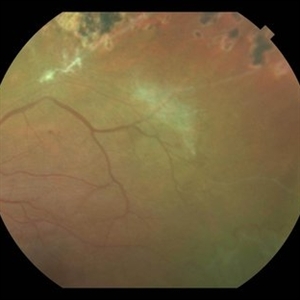

Sickle Cell Retinopathy with Sea Fans

Color fundus photograph of a 40-year-old man with African heritage and sickle SC disease. A sea fan (white) is present along the superotemporal arcade adjacent to an area of ischemia.

Photographer: Geoffrey Emerson, MD, PhD, Retina Center, Minneapolis

Condition/keywords: sea fan, sickle cell retinopathy